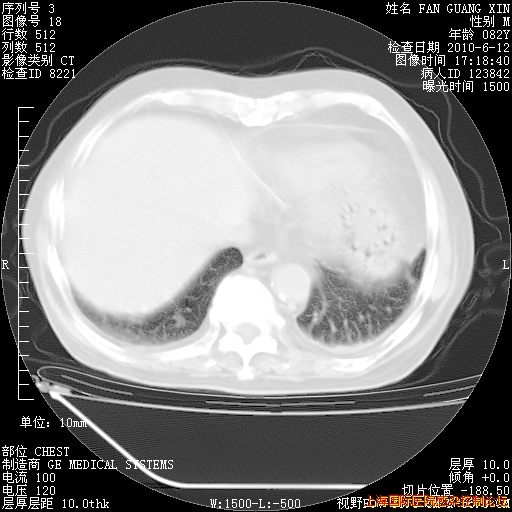

今天复查CT

今天CT

整整相隔30天的肺部CT好像有所好转啊。甲强龙减量第3天,需要观察体温。